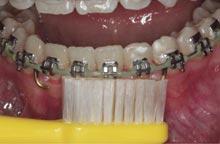

The placement of fixed attachments and auxiliaries upon a tooth surface increases the risk of plaque accumulation ( Figure 1 ). This occurs through disruption of the oral cavity’s natural self-cleaning mechanism, and such appliances act as both a barrier to oral hygiene and local retentive factors, thereby hindering hygiene practices.1

Several studies have investigated the efficacy of manual and electric toothbrushes (Figures 2a and 2b). Some authors have found electric to be more effective than manual models,5 while others could not reproduce these conclusions. Conversely, the opposite has also been demonstrated.6 A recent systematic review and meta-analysis on this topic emphasised the equivocal nature of the current evidence.7 Various manual toothbrush designs have also

been investigated (Figures 3a and 3b). Research has found no significant difference in plaque removal effectiveness between different manual designs.8 There is some evidence that new models of electric toothbrushes may be more effective than traditional ones.

The current consensus is that there is insufficient evidence to advocate for the use of electric over manual toothbrushes, or for any one manual design, for improving plaque control in FA patients. Therefore, the dental team should aim to improve patients’ knowledge and awareness, in conjunction with other aids, rather than focusing on the type of brush used.